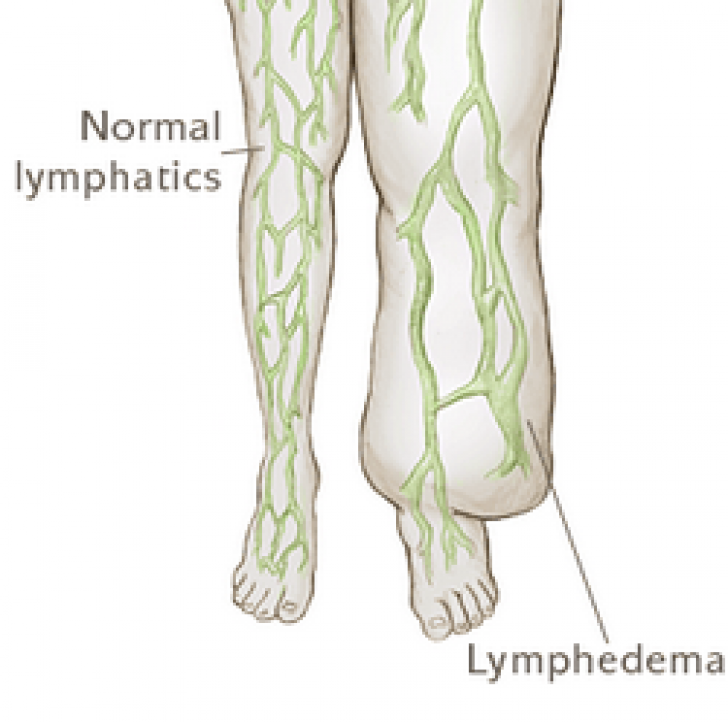

Изображения и схемы: как выглядит лимфа